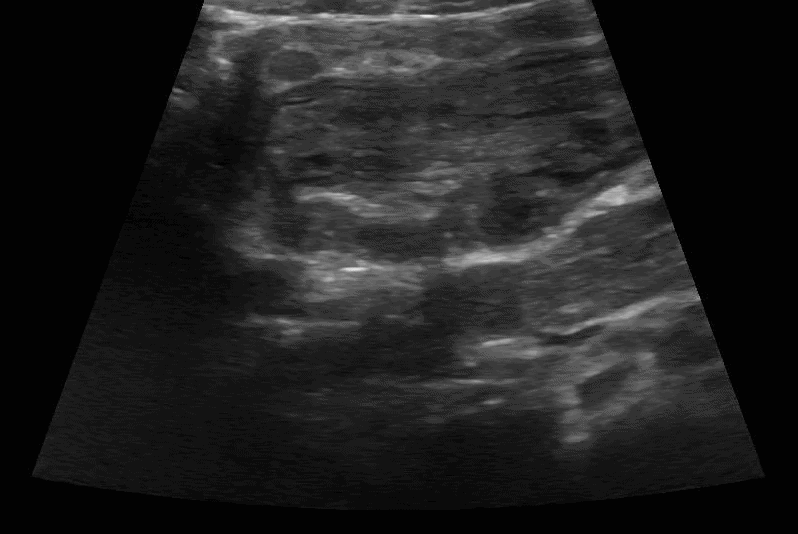

Scanning technique: When evaluating for intussusception with point-of-care ultrasound (POCUS), the infant is placed supine and a high-frequency linear transducer is used initially, with a curvilinear probe available for deeper or larger fields of view. The abdomen is scanned systematically in transverse and longitudinal planes, starting in the right lower quadrant and sweeping through the right upper quadrant, epigastrium, and left abdomen, with particular attention to the periumbilical region and right upper quadrant, where intussusception is most commonly identified. Graded compression is applied to displace bowel gas and improve visualization. On POCUS, intussusception classically appears as a “target” or “donut” sign in the transverse view, characterized by concentric hypoechoic and hyperechoic rings, and as a “pseudokidney” or “sandwich” sign in the longitudinal view. Associated findings may include proximal bowel dilation, free fluid, or absent peristalsis within the involved segment.

Clip 4: Intussusception short axis.

Clip 5: Intussusception short axis.